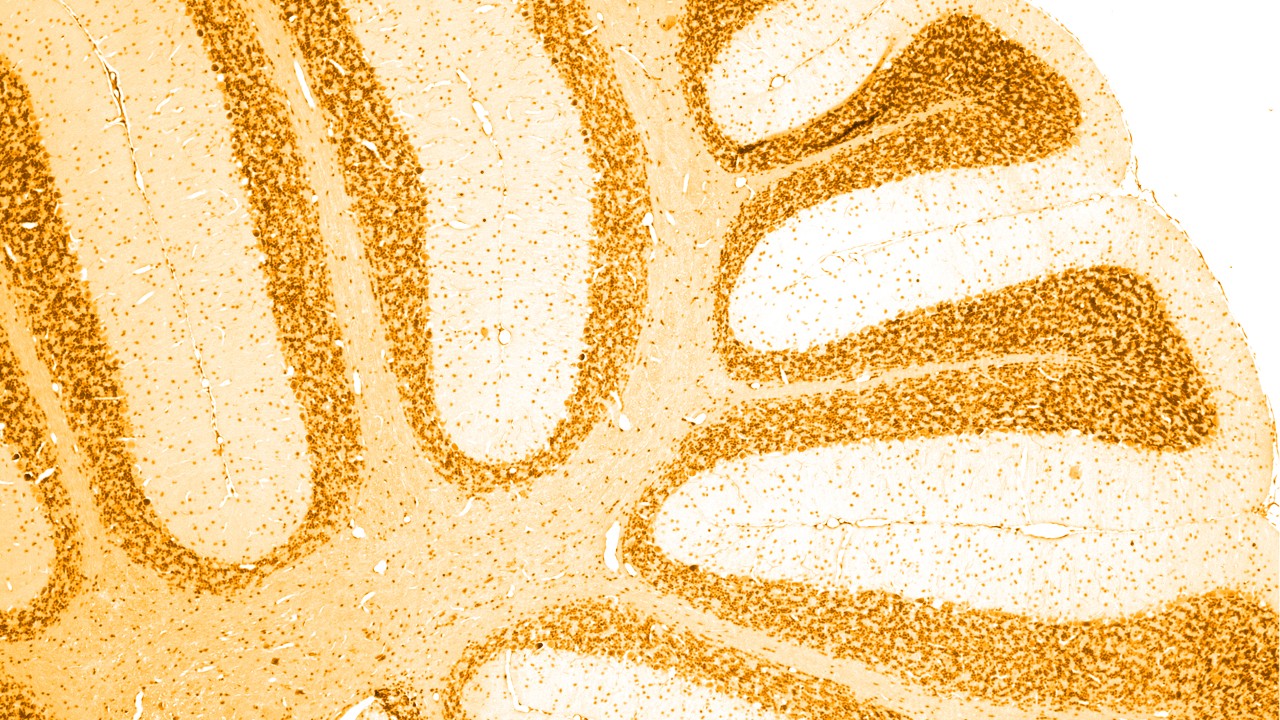

Neurologie

Neurologische Erkrankungen verstehen

Neurologische Erkrankungen betreffen das zentrale und periphere Nervensystem und damit das Gehirn, das Rückenmark und alle Nerven und Muskeln, die die Körperfunktionen regulieren und koordinieren.